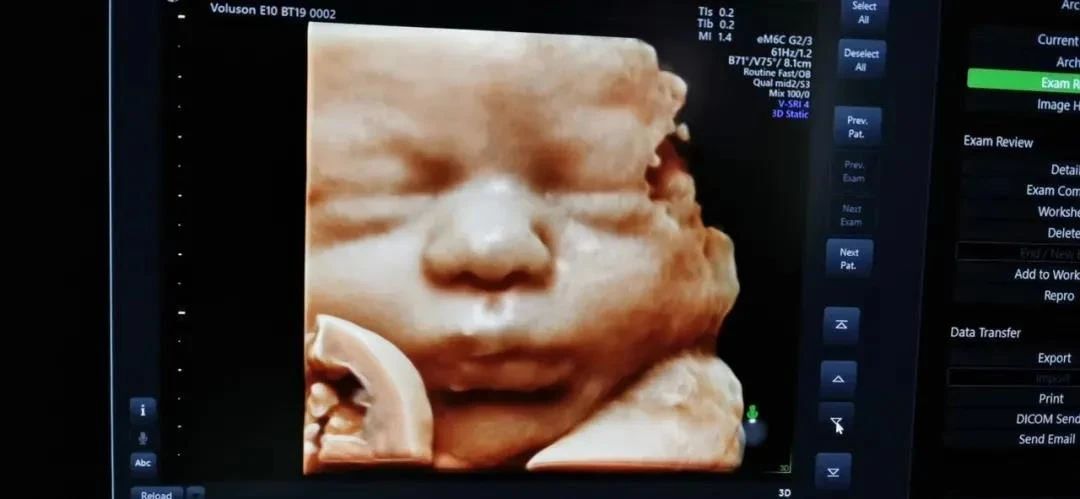

其次,安琪儿使用的彩超设备是ge-e10,也是成都更早拥有ge-e10的医疗机构,胎儿排畸检查更强大,独立成像更清晰。孕妈妈还可以通过四维彩超获得宝宝人生第一张照片哦!